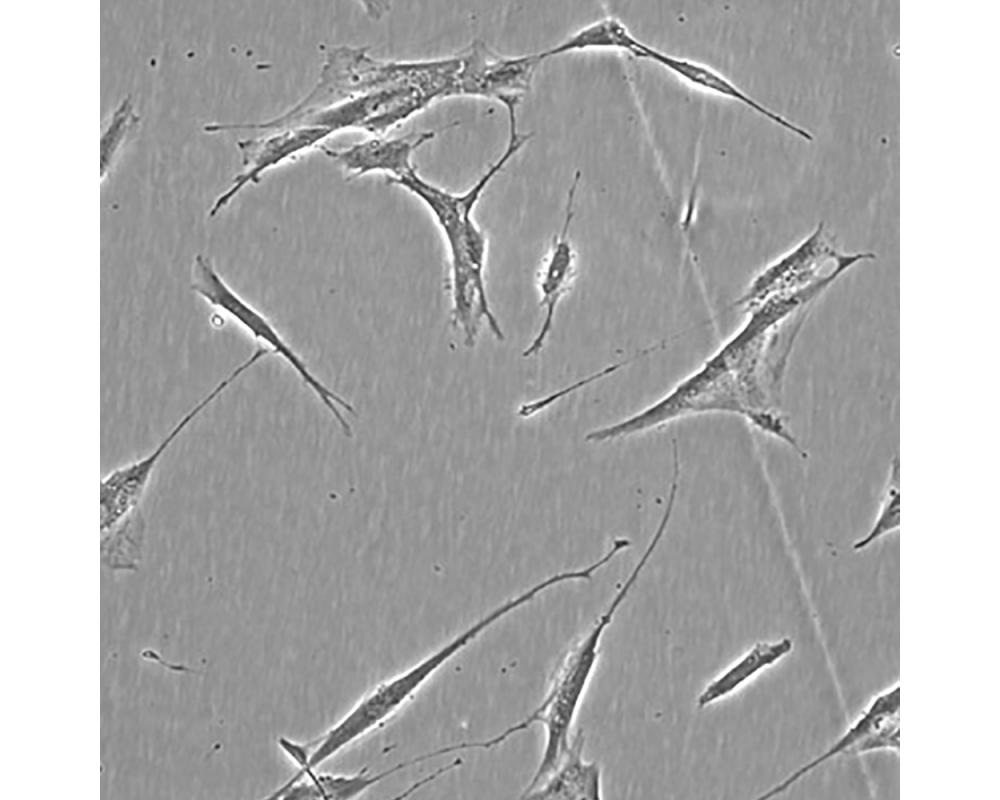

產(chǎn)品名稱(chēng) Hs 606.T

中文名稱(chēng) 人乳腺癌細(xì)胞

組織來(lái)源 乳腺癌;女性

生長(zhǎng)特性 貼壁